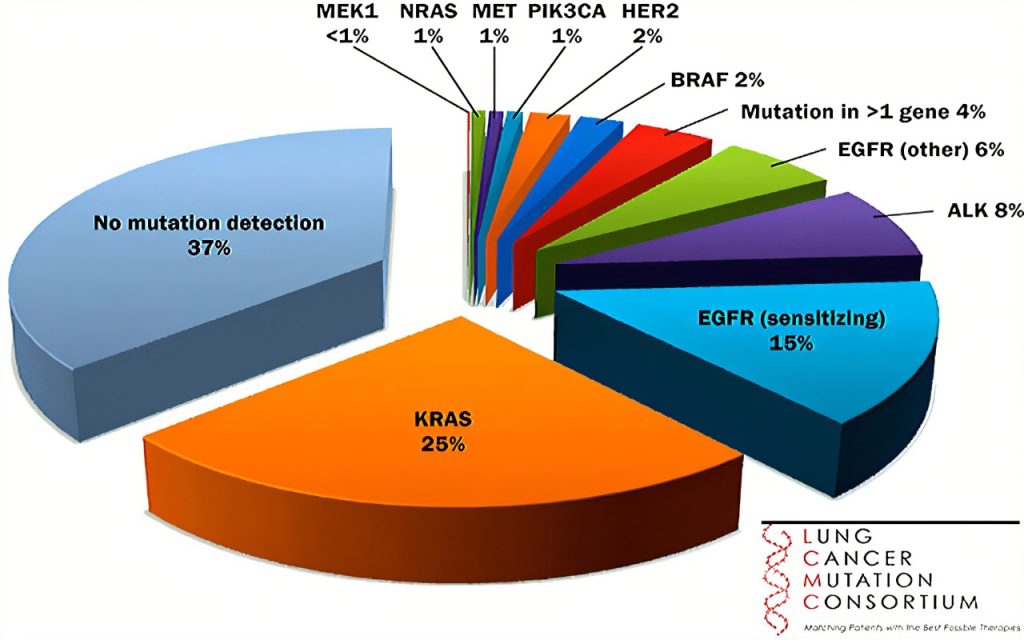

KRAS | p.G12D,p.G12V,p.G12C,p.G13D | 曲美替尼/司美替尼/Sotorasib/Abemaciclib |

3.KRAS(Kirsten rat sarcoma virus)基因,其全称为K-Ras,它是RAS/MAPK通路的一部分。

- KRAS基因属于一类被称为致癌基因的基因。当发生突变时,这些基因有潜力使正常细胞变成癌细胞。

- KRAS基因位于Ras家族的致癌基因中,其中还包括另外两个基因:HRAS和NRAS。这些蛋白质在细胞分裂、分化和自我毁灭(凋亡)中起着重要作用。